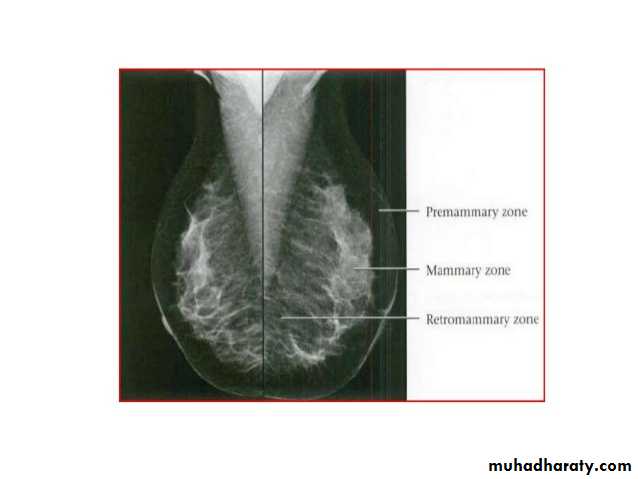

Breast density & who can U detect a mass lesion

Your mammogram report must take in consideration & assessment the breast density. Breast density is based on how fibrous and glandular tissue tissues are distributed in your breast, vs. how much of your breast is made up fatty tissue.

Dense breasts are not abnormal, but they are linked to a higher risk of breast cancer. We know that dense breast tissue can make it harder to find cancers on a mammogram. Still experts do not agree what other tests, if any, should be done in addition to mammograms in women with dense breasts who aren’t in a high-risk group (based on gene mutations, breast cancer in the family, or other factors